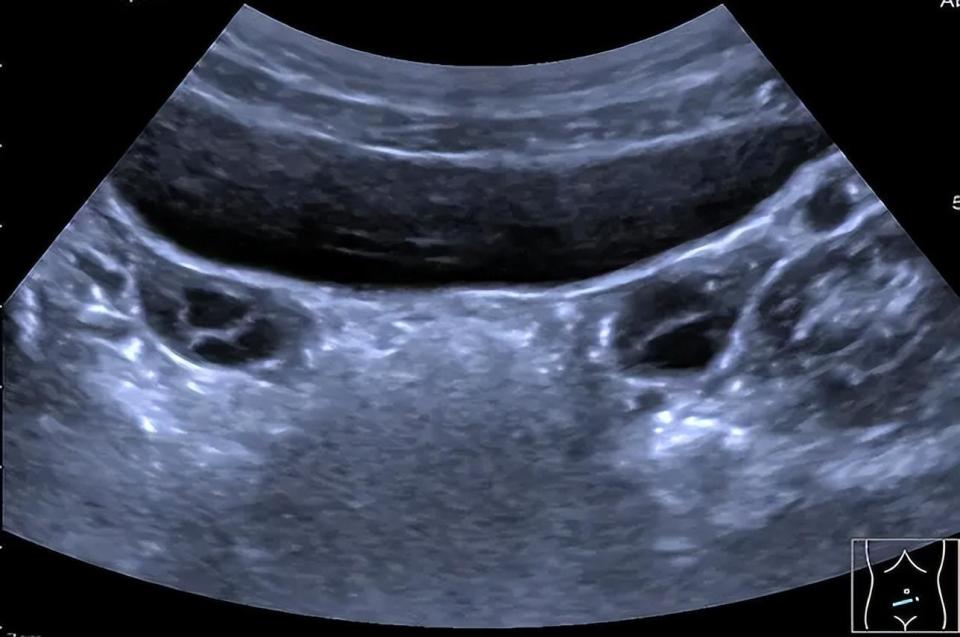

图片

▲左侧卵巢体积约4.9ml,内见4个直径大于4mm卵泡